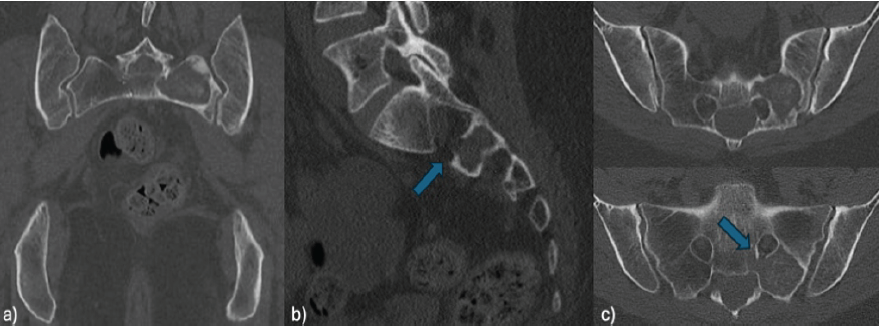

The computed tomography (CT) identified a lytic and eccentric lesion of chondroid characteristics, with well-defined borders and a locally aggressive behavior, located within the left sacrum in the S1-S2 interforaminal region, measuring 39 × 30 × 23 mm. The lesion had a partial extension to the left sacral body and a small focus of cortical disruption in the anterior aspect of the S2 foramen (Fig. 2).

Figure 2: Pelvic computed tomography scan in axial (a), coronal (b), and sagittal (c) views. Lytic lesion in the left sacrum with cortical disruption in the anterior aspect of the S2 foramen (arrow).